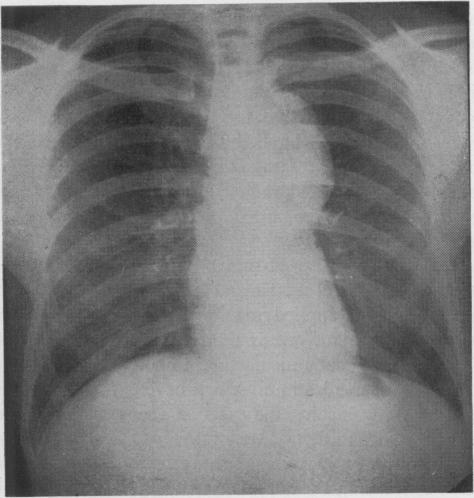

Blades C B

Ann Surg. 1946 May;123(5):749-64.